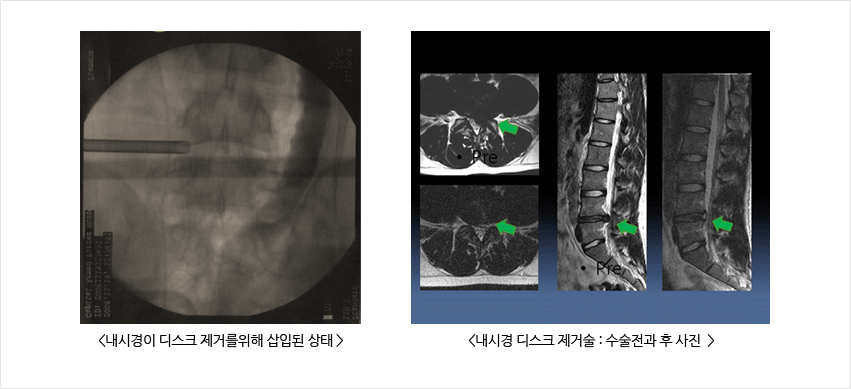

통증이 심한 경우는 병원에서 약물 처방이나 물리치료를 꾸준히 받게 되면 증상이 다량 완화가 됩니다. 그리고 허리 근육이 발달되면 척추로부터 전달되는 충격이 덜해질 수 있다고 합니다. 따라서 허리디스크 환자에게 운동은 필수라고 말할 수 있겠습니다. 허리가 이미 튼튼한 상태라도 운동으로 허리 근육을 강화시키면 허리디스크를 미리 막을 수 있게 됩니다. 이렇게 하여 허리디스크 증상과 원인에 대하여 이야기해보았습니다. 현재 허리디스크로 고생하시는 사람들에게 위와 같은 정보들이 약간이라도 도움이 될 수 있기를 희망합니다.디스크가 더 나빠지는 것을 예방하고 완화시키기 위한 것은 체중을 줄이며, 허리 근육을 키워야 합니다. 체중은 디스크에 압력으로 작용하고 디스크가 터지거나 뒤로 밀려 나오게 하는데, 등 근육이 발달할 경우 이를 막을 수 있다고 해요. 그리고 충격이 가해지는 상황에서 충격 흡수 역할도 하게 되기 때문에 근육을 키우는게 중요합니다.

허리를 뒤로 펴는 신전 동작이 허리디스크 회복을 가속화 해요. 활배근을 강하게 만들고 사람마다 복대만 차도 허리가 아픈 경우가 있으므로 단계적인 운동을 추천해요. 의자에 앉아 있을 떄는 의자 등받이가 전만으로 휘어져있으며 허리 쿠션을 쓰시는 걸 권장드리겠습니다. 물건을 들어 올릴 때도 허리를 숙이지 않고 런지자세로 들어 올리거나 천천히 해야 해요. 티비를 보거나 잘 때는 옆으로 눕는 것보다는 엎드려서 누워 있는 게 요추 전만에 좋답니다.